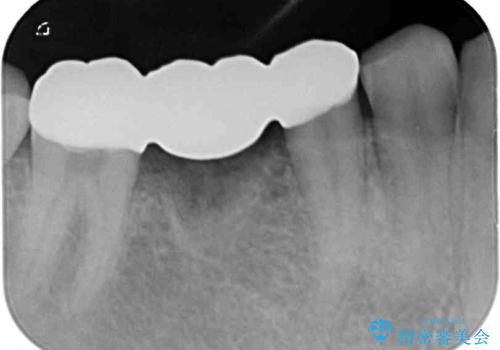

放置した虫歯 奥歯のオールセラミックブリッジ治療

抜歯部分の治癒を待つ間に、全体的な汚れの多さを改善する指導と処置を進め、その後オールセラミックブリッジにて補綴治療を行うこととしました。

神経を取り除く可能性のあった奥歯ですが、何とか保存することができました。

奥歯はしっかりと治療することができたので、今後は虫歯予防と他の要治療歯の処置を行っていくことになります。